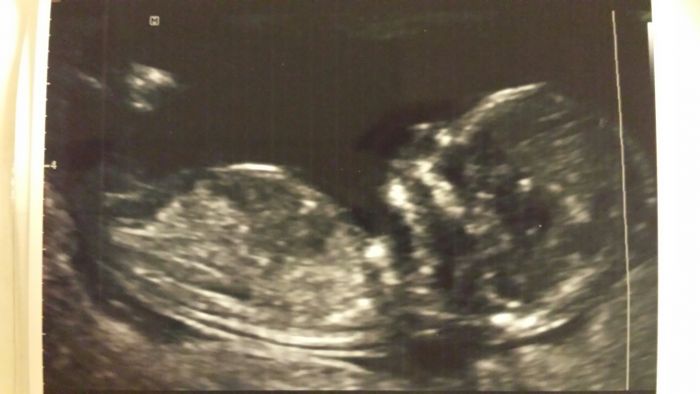

Tak už i my máme dnes po screeningu a vypadá to na nevěstu pro všechny ty vaše chlapečky :) A já byla uvnitř naprosto přesvědčená, že je to kluk :) Měří 7 cm a viděla jsem srdíčko, žaludek, páteř, obě ručičky i nožičky...

Přikládám fotku maličké, celou dobu si na nás otvírala pusu :)